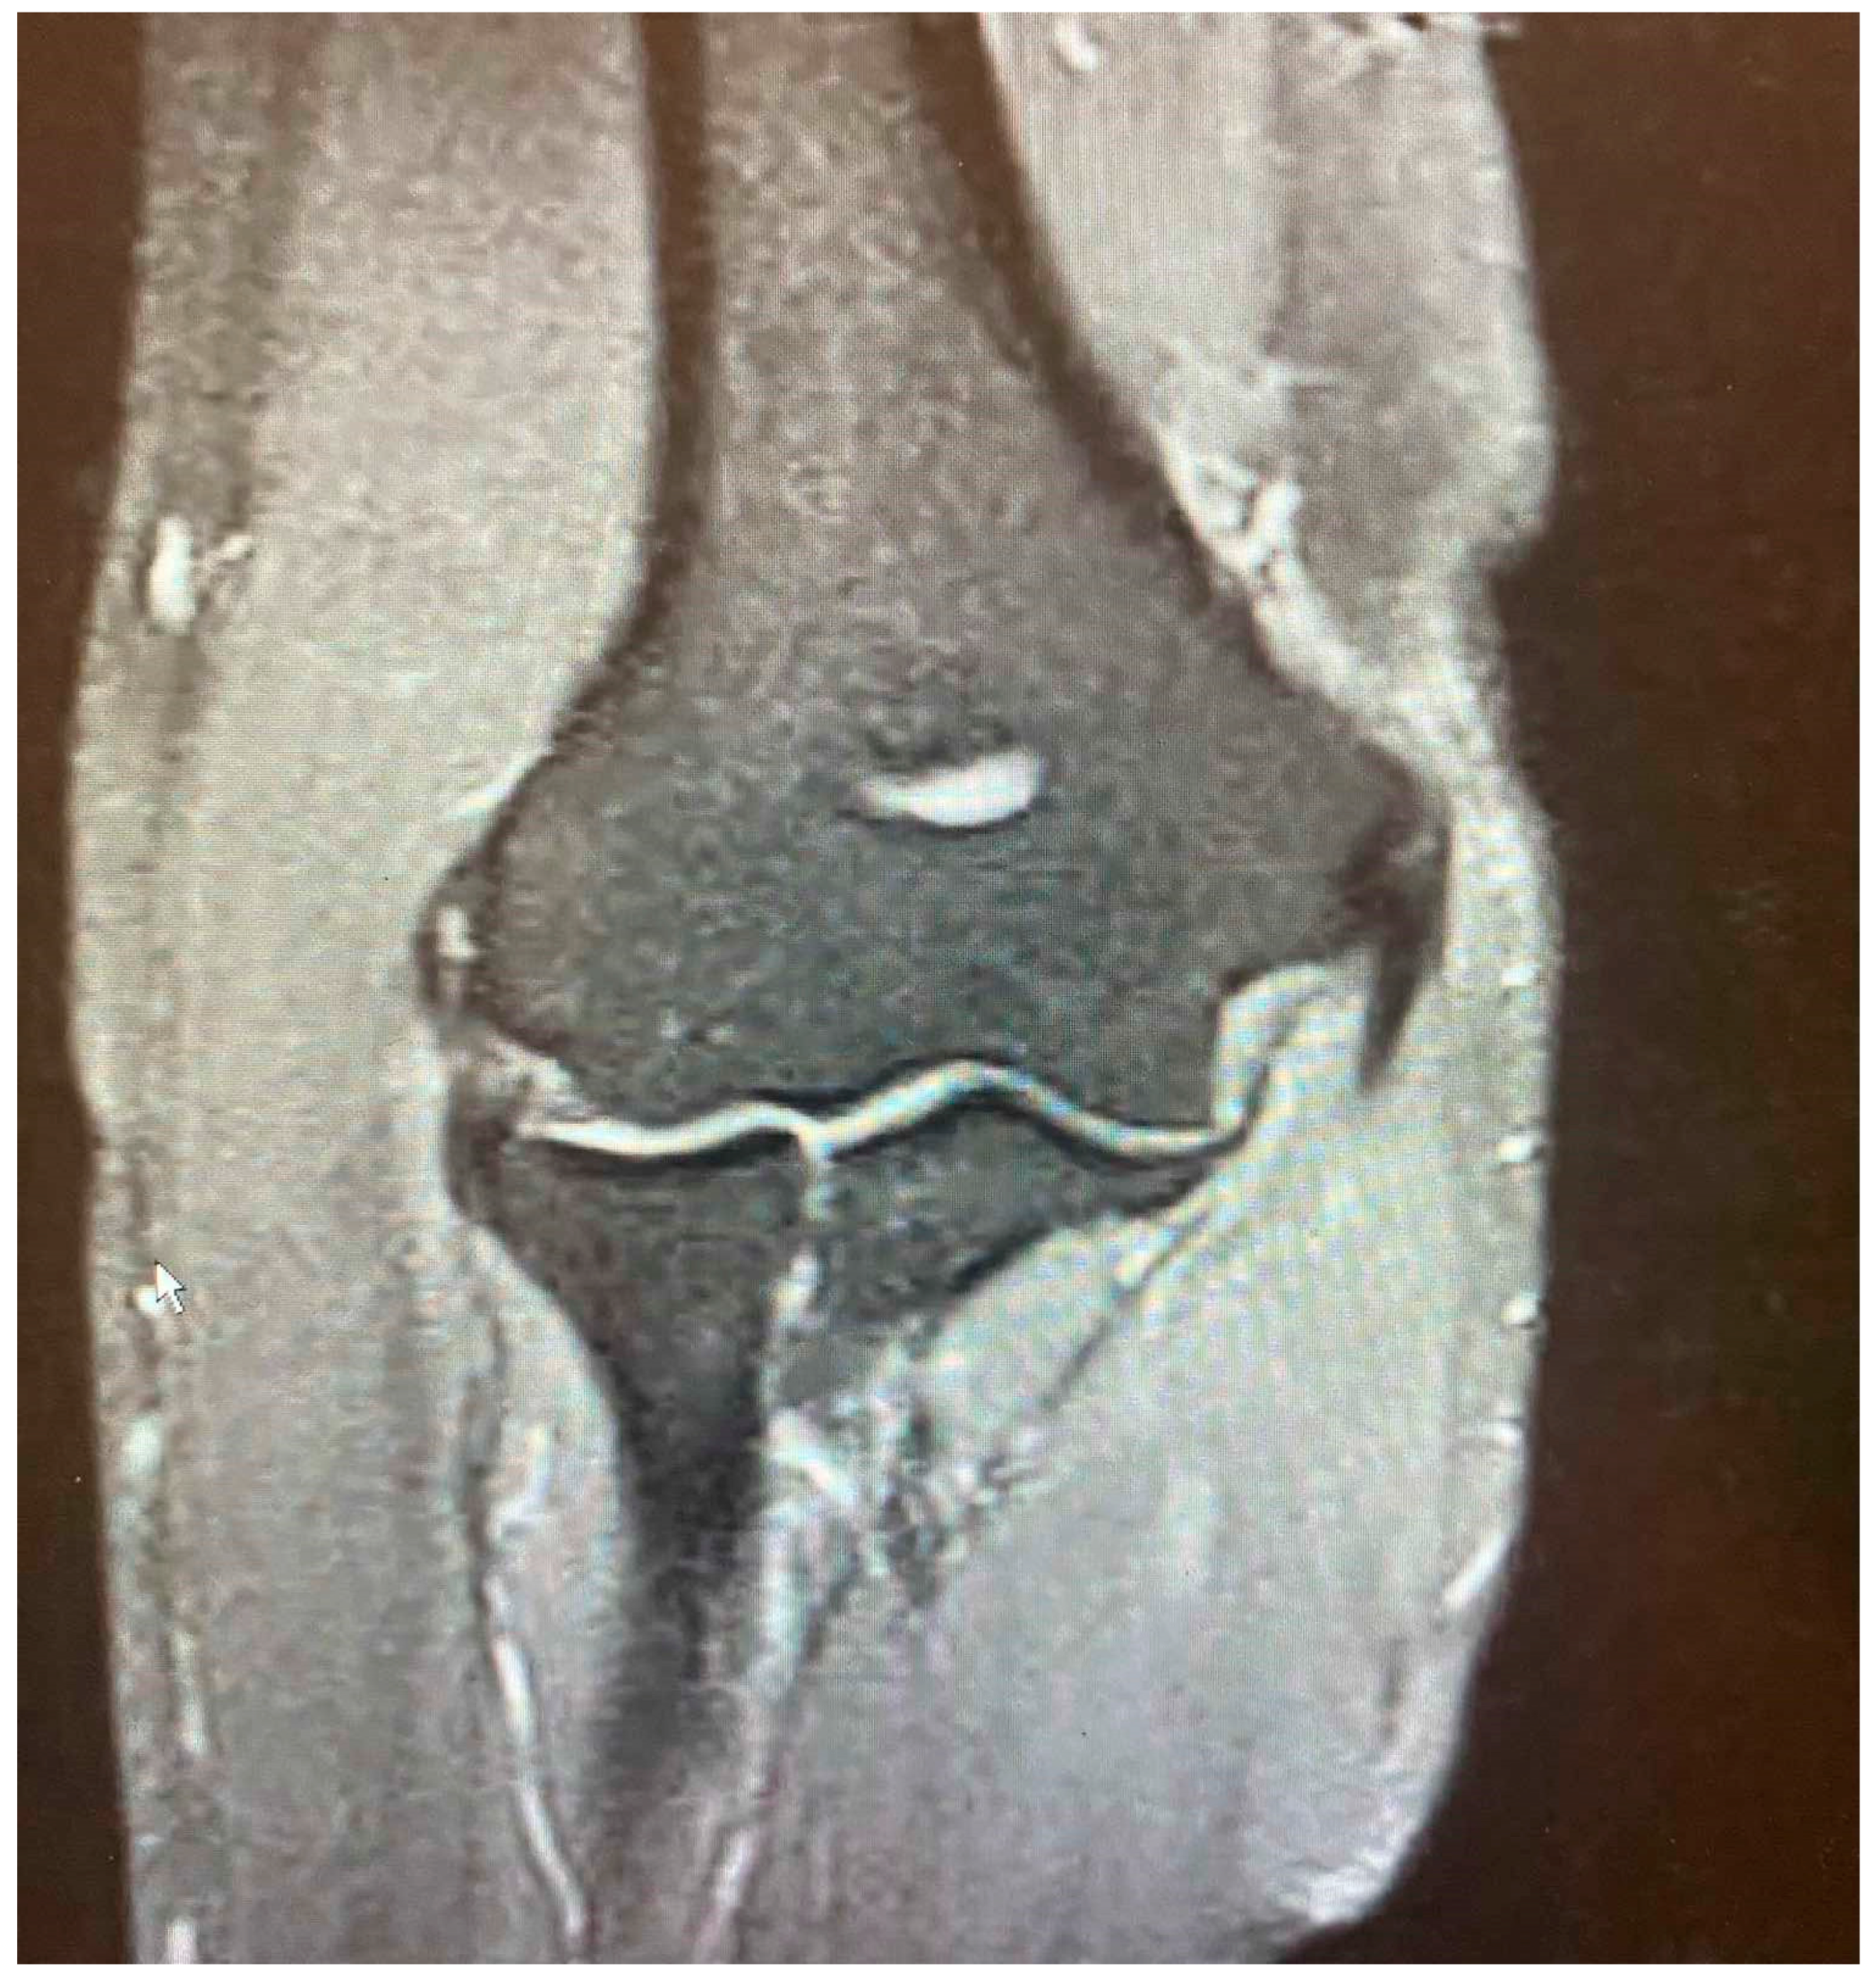

- It is contingent on the integrity of the CEO, whether it is intact, has a moderate or extensive partial tear, or is completely ruptured with or without retraction. This evaluation can be conveniently conducted via MRI.